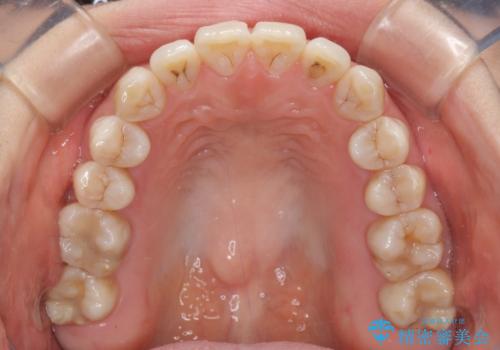

話しにくいオープンバイト インビザラインによる矯正治療

- 前歯の上下スペースによる話しにくさを気にして来院された患者様です。

インビザラインにより上下の前歯の隙間を閉じていくこととしました。

上下の奥歯を圧下させるようにすることで、前歯を接触させるように計画しました。

隙間に舌が入り込むことが話しにくさに繋がっていたため、舌の筋肉のトレーニングも並行して行い、話しにくさの改善と後戻りの抑制を図りました。